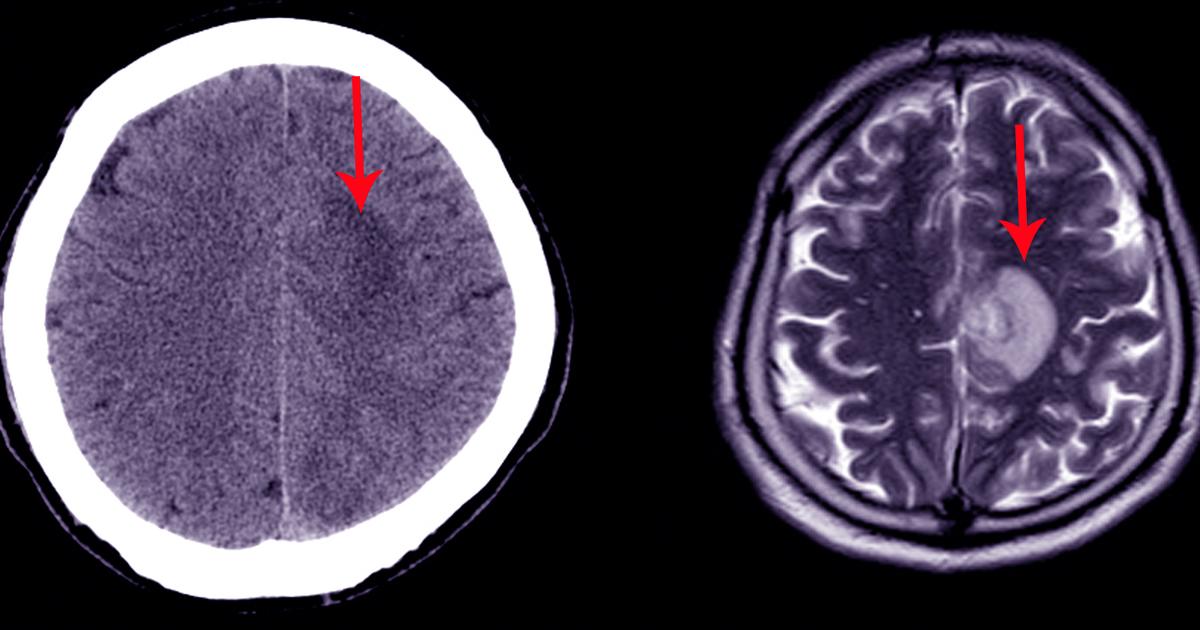

A subarachnoid hemorrhage develops when there is bleeding in the subarachnoid space. This is the area between the brain and the surrounding membrane. The hemorrhage has a sudden onset. The first symptom is usually a severe headache that may be accompanied by nausea or vomiting. Patients experiencing this hemorrhage might briefly lose consciousness. In some cases, patients may feel a popping sensation in their head just before the hemorrhage begins. Seizures, confusion, and numbness throughout the entire body could occur after this.

Serious head injuries such as falls and injuries from car accidents could lead to a subarachnoid hemorrhage. Blood thinners or an underlying medical condition such as an arteriovenous malformation can also cause this condition. This condition is considered a medical emergency. At the hospital, doctors will perform a physical examination and take CT scans or MRI scans. A cerebral angiography test may be performed as well. Surgical procedures will be carried out to reduce the buildup of pressure in the brain and to stop the bleeding.